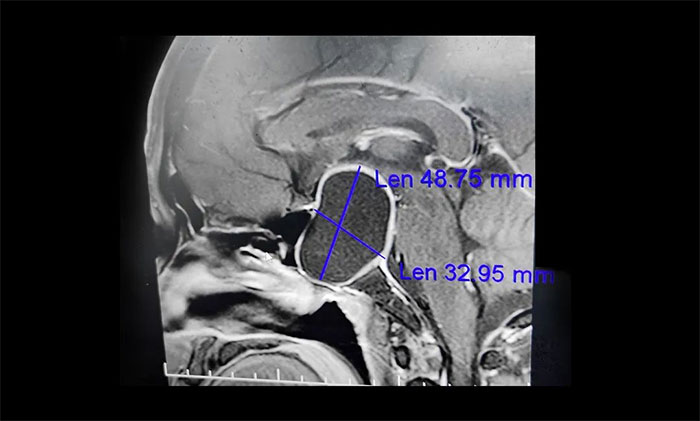

▲垂體大腺瘤伴囊變,壓迫視神經,導致視野缺損、視力下降

“醫生,我已經做了白內障手術,怎麼眼睛還是看不清東西呢?”半年多前,67歲宋阿姨的因視力模糊和下降到眼科就診,被確診為右眼白內障。當地眼科醫生為宋阿姨進行了白內障手術。本以為手術後,視力便可慢慢恢復正常。誰料,右眼視力卻愈發“不好使”,左眼的視力也下降明顯。通過對宋阿姨眼睛的複查,雖然白內障得到改善,但患者視力仍很差,雙眼外側的餘光變窄,因此醫生高度懷疑他視力下降的原因可能跟腦部病有關,因此建議宋阿姨到神經內科做進一步檢查。最終查出4公分大的巨大垂體瘤。